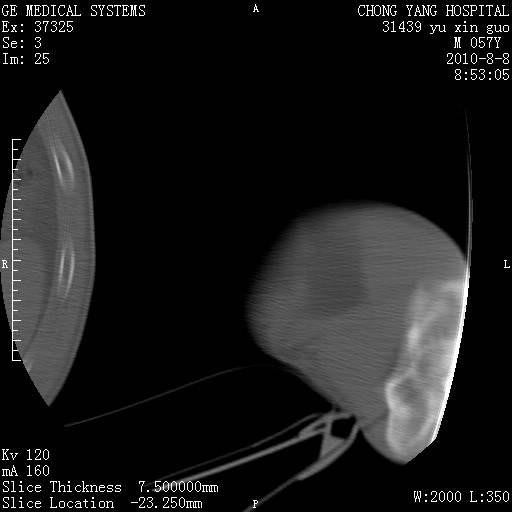

标题: CT28267:M57Y 上臂包块8年余。 [打印本页]

标题: CT28267:M57Y 上臂包块8年余。

包膜光滑、完整的脂肪密度肿块,支持脂肪瘤。